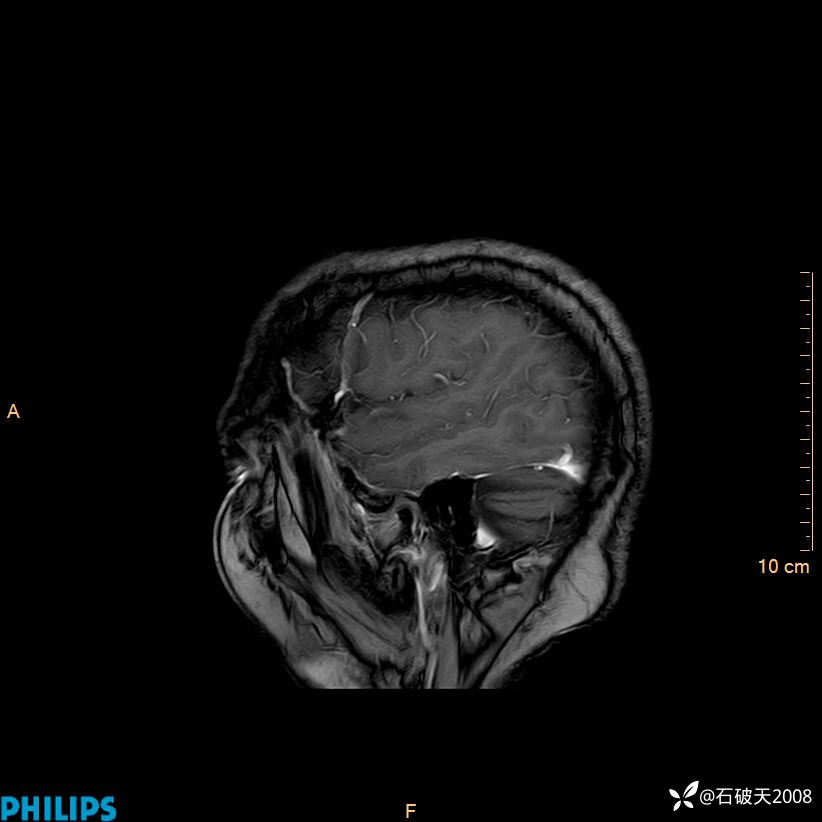

2024.2.21MR

增强冠状位